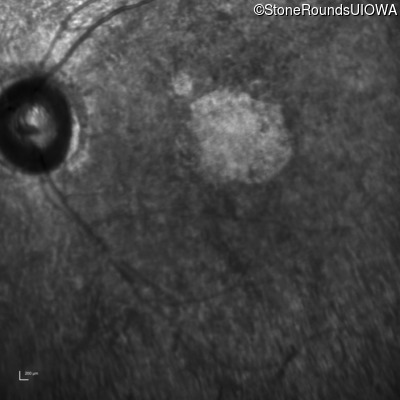

This 47 year old woman was born with a supernumerary digit on the ulnar side of both hands. As a young child, her best corrected visual acuity was completely normal. She had no difficulties with her vision until age 30 when her visual acuity could no longer be corrected to 20/20 and she began to notice some night blindness.

The clinical features supporting the diagnosis of Bardet Biedl syndrome in this patient include: bone-spicule-like pigmentation, narrowed arterioles and macular atrophy on ophthalmoscopy; photoreceptor loss on OCT; ulnar polydactyly, obesity, abnormal cognition, hypertension; and, normally sighted parents.